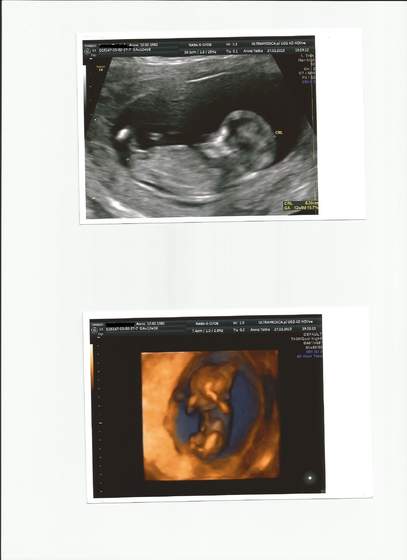

ASTA to nie rozumiem z jakich badań rezygnujesz? bo o przeziornośc pytasz czy można zrezygnowac, a to właśnie to są te badania robione w 11-13tyg ciąży... Lekarz nawet nie pyta czy chcesz je robic czy nie... one są w podstawowym kalendarzu badań... jak mocz i krew...